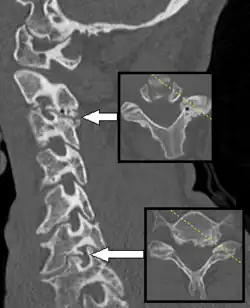

Radiculopathy most often is caused by mechanical compression of a nerve root usually at the exit foramen or lateral recess. It may be secondary to intervertebral disk herniation (most commonly at C7 and then the C6 level), degenerative disc disease, osteoarthritis, facet joint degeneration/hypertrophy, ligamentous hypertrophy, spondylolisthesis, or a combination of these factors.[3][4] Other possible causes of radiculopathy include neoplastic disease, infections such as shingles, HIV, or Lyme disease, spinal epidural abscess, spinal epidural hematoma, proximal diabetic neuropathy, Tarlov cysts, or, more rarely, sarcoidosis, arachnoiditis, tethered spinal cord syndrome, or transverse myelitis.[3]

If symptoms do not improve after 4–6 weeks of conservative treatment, or the person is more than 50 years old, further tests are recommended.[3] The American College of Radiology recommends that projectional radiography is the most appropriate initial study in all patients with chronic neck pain.[13] Two additional diagnostic tests that may be of use are magnetic resonance imaging and electrodiagnostic testing. Magnetic resonance imaging (MRI) of the portion of the spine where radiculopathy is suspected may reveal evidence of degenerative change, arthritic disease, or another explanatory lesion responsible for the patient's symptoms. Electrodiagnostic testing, consisting of NCS (nerve conduction study) and EMG (electromyography), is also a powerful diagnostic tool that may show nerve root injury in suspected areas. On nerve conduction studies, the pattern of diminished compound muscle action potential and normal sensory nerve action potential may be seen given that the lesion is proximal to the posterior root ganglion. Needle EMG is the more sensitive portion of the test, and may reveal active denervation in the distribution of the involved nerve root, and neurogenic-appearing voluntary motor units in more chronic radiculopathies. Given the key role of electrodiagnostic testing in the diagnosis of acute and chronic radiculopathies, the American Association of Neuromuscular & Electrodiagnostic Medicine has issued evidence-based practice guidelines, for the diagnosis of both cervical and lumbosacral radiculopathies.[14][15] The American Association of Neuromuscular & Electrodiagnostic Medicine has also participated in the Choosing Wisely Campaign and several of their recommendations relate to what tests are unnecessary for neck and back pain.[16]

While conservative approaches for rehabilitation are ideal, some patients will not improve and surgery is still an option.[23] Patients with large cervical disk bulges may be recommended for surgery; however, most often, conservative management will help the herniation regress naturally.[24] Procedures such as foraminotomy, laminotomy, or discectomy may be considered by neurosurgeons and orthopedic surgeons. Regarding surgical interventions for cervical radiculopathy, the anterior cervical discectomy and fusion procedure is more commonly performed than the posterior cervical foraminotomy procedure.[25] However, both procedures are likely equally effective and without significant differences in their complication rates.[25]